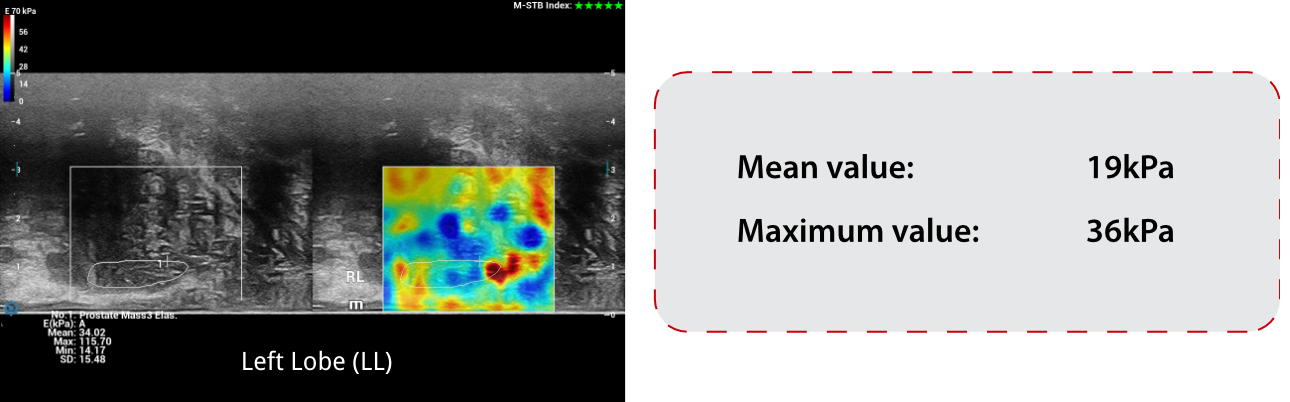

Elastography Findings:

SWE ŌĆō Shear Wave Elastography:

The stiffness measurement results on PZ of RL were quite soft when compared with RL.

- While SWE showed normal stiffness measurements of LL, which mean stiffness value was 19kPa and max stiffness value was 36kPa.